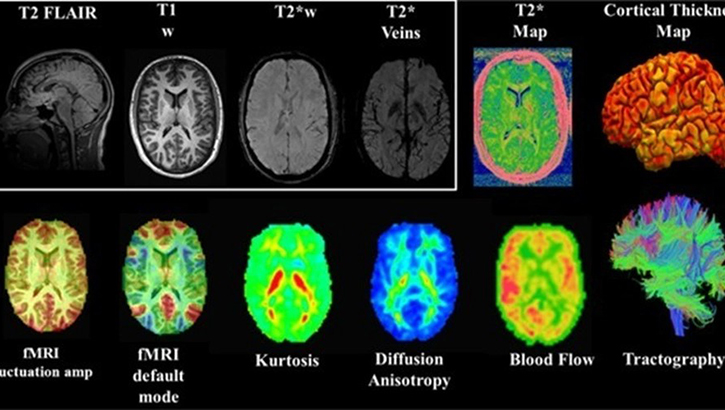

Image of MRI brain scans. CARE MRI integrating multimodal imaging biomarkers of changes in brain structure and function. Mild traumatic brain injury, or concussion, is a major issue of concern in the military, as well as within the sports community. The NCAA-DoD Grand Alliance CARE Consortium, works to better understand sports-related concussions among varsity athletes including students at the four Military Service Academies.

The study is testing biomarkers, or measurable signals in blood and/or imaging, that may reveal how the brain responds to concussions, repeated head impacts, and other health risk factors. These include advanced scans like MRI and PET (positron emission tomography), as well as blood-based markers that show inflammation or damage long before symptoms appear.